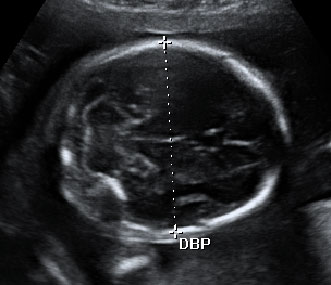

Ecografía Embarazo 2D y 3D - SEMANA 20